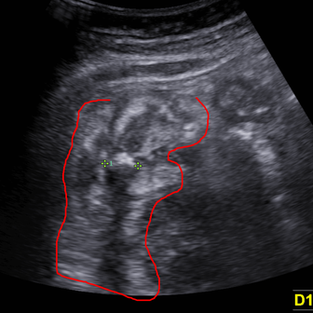

우상복부에/압통의 부위와 일치하여 두개의 저에코 경계로 둘러진 원형 고에코가 있는 구조에 후방으로의 ring-down artifact가 관찰됨

벽의 비후는 일부 의심되나 뚜렷하지 않음.

주변으로 대장부변 지방의 염증성 고에코성 변화를 관찰할 수 있다.